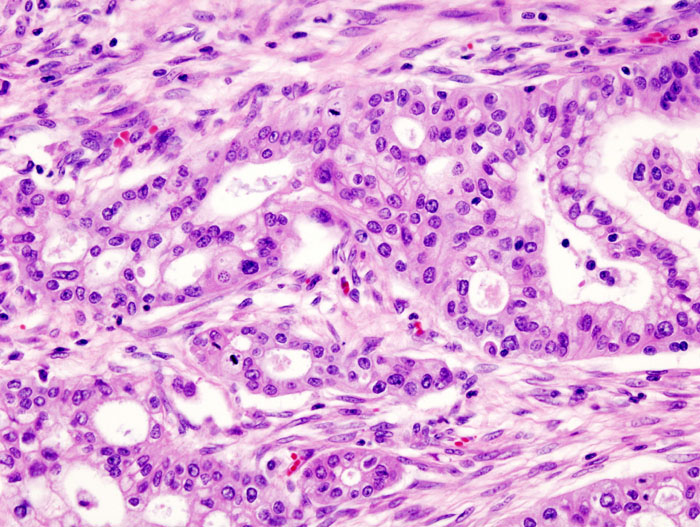

A second, separate paper was published this month in the journal Scientific Reports. This study explains how scientists from University College London (UCL) designed a new chemical compound, able to reduce the growth of pancreatic cancer tumours in mice by 80%. This compound – known as MM41 – can block faulty genes by targeting little knots in their DNA, called quadruplexes, which are very different from normal DNA and are especially found in faulty genes. It is confirmed that MM41 has a strong inhibiting effect on two genes – k-RAS and BCL-2 – both of which are found in the majority of pancreatic cancers. The UCL team, led by Professor Stephen Neidle, conducted a small-scale trial involving two groups of eight mice with pancreatic tumours using different doses of the compound, twice a week for 40 days. A further control group received no treatment. The tumours in the group given the larger dose decreased by an average of 80% during the treatment period, and after 30 days, regrowth stopped in all the mice. For two of the mice in this group, the tumour disappeared completely with no signs of regrowth at all following the end of treatment, for a further 239 days (equivalent to the rest of their average natural life span). Analysis of the mice tumours showed that the MM41 compound had been taken up into the nucleus of the cancer cells, showing that it was able to effectively target the pancreatic cancer tumour. No significant side effects were observed on the mice during the study: there was no damage to other tissue or organs and none of the mice showed any significant weight loss. Discussing the results, Neidle explained: "This research provides a potentially very powerful alternative approach to the way that conventional drugs tackle pancreatic cancer, by targeting a very specific area of the DNA of faulty genes. One of the genes that MM41 blocks – the BCL-2 gene – is involved in regulating apoptosis, the body's natural process which forces cells to die if they become too damaged or unhealthy to be repaired. BCL-2 is present in high amounts in many tumours and helps cancer cells to survive, but when the BCL-2 gene is blocked by MM41 in mice, the cancer cells succumb to apoptosis and die." Neidle stresses that although these results are exciting, MM41 is not ideal for trialling in humans and further refinements are needed: "We are now working to optimise this class of compounds, but it's clearly worthy of further investigation for potential use in treating pancreatic cancer in people."